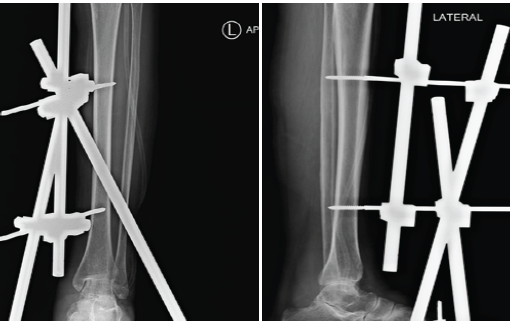

Bone graft (autologous cancellous) was harvested from the iliac crest and filled inside the defect. Fig. 5: Temporary stabilization was done with an external fixator (delta frame).

Figure 5: Delta frame applied after debridement.

Thorough debridement of the infected tissue was done with a curette, till fresh bleeding was noted. Autologous bone graft was given and temporary stabilization with an external fixator was given. The patient was started on Amphotericin B for 6 weeks. Patient was advised non-weight-bearing walking (walker-assisted) for 3 weeks. (Fig. 9).